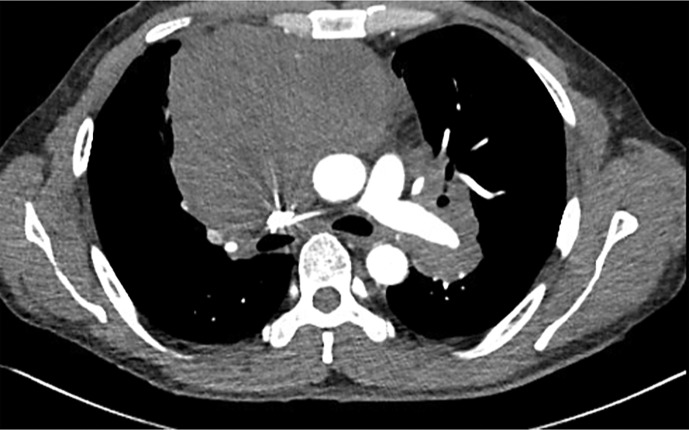

Case report: We present a rare case of PMBCL in a 39-year-old male with a bulky mediastinal mass that resulted in superior vena cava thrombosis and cardiac tamponade. Diagnostic discordance between histopathological and molecular data led to a delay in interception of this entity. Histopathology findings were suggestive of spindle-cell neoplasm. Contrastingly, next-generation sequencing (NGS) and immunohistochemistry (IHC) yielded a molecular diagnosis of PMBCL. IHC staining revealed that the atypical cells were positive for CD20, PAX5, CD79a, CD30, CD23, MUM1, and weakly positive for MAL (myelin and lymphocyte) protein. NGS showed increased expression of TNFRSF8 and CD274 genes, which encode CD30 and PDL1 proteins, respectively. The patient was successfully treated with the R-Hyper-CVAD protocol without consolidative radiotherapy.